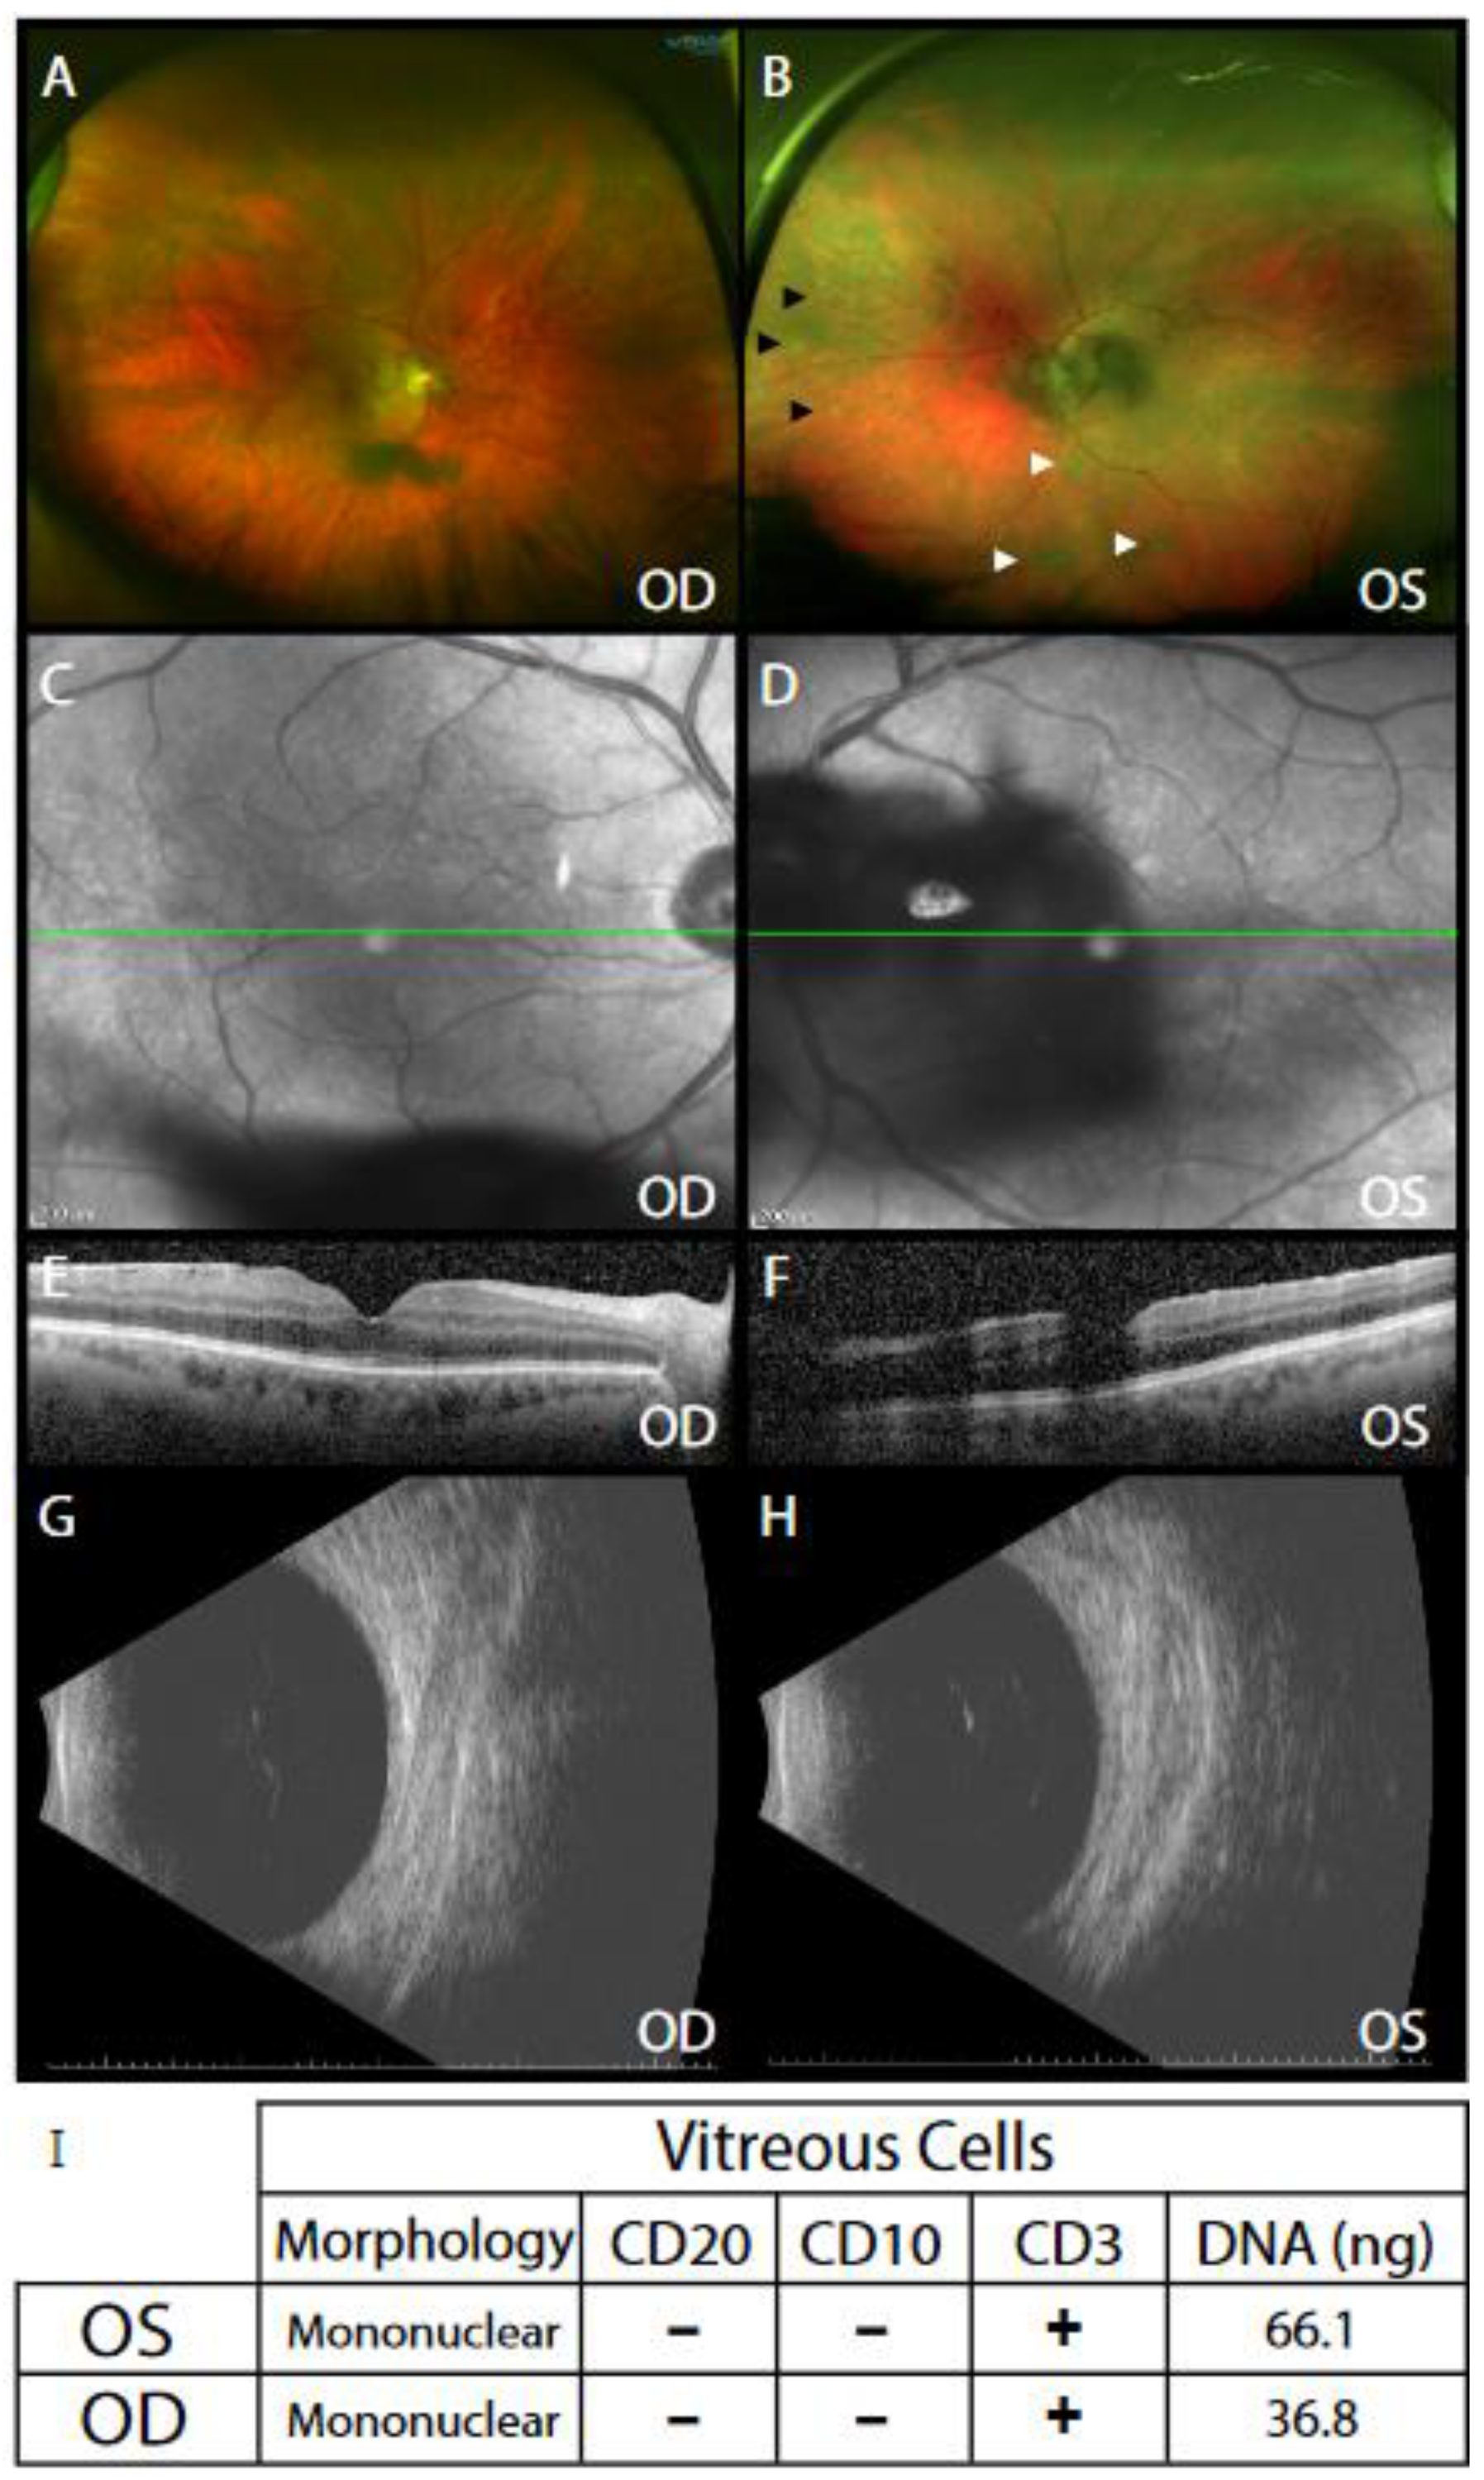

Cani, A.K.; Toral, M.A.; Balikov, D.A.; Betz, B.L.; Hu, K.; Liu, C.-J.; Prifti, M.V.; Chinnaiyan, A.M.; Tomlins, S.A.; Mahajan, V.B.; et al. Molecular Characterization of a Rare Case of Bilateral Vitreoretinal T Cell Lymphoma through Vitreous Liquid Biopsy. Int. J. Mol. Sci. 2021, 22, 6099. https://doi.org/10.3390/ijms22116099